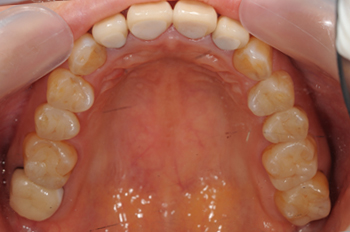

銀歯の除去と金属を使用しない補綴治療

治療の内容:銀の詰め物をセラミック13本をにやり変え、銀の被せ物(臼歯)を2本と前歯2本のやり変え

期間:1年4ヶ月

費用:1,128,600円(税込み)※自由診療

リスク:セラミックは陶材であるため、割れることがあります。